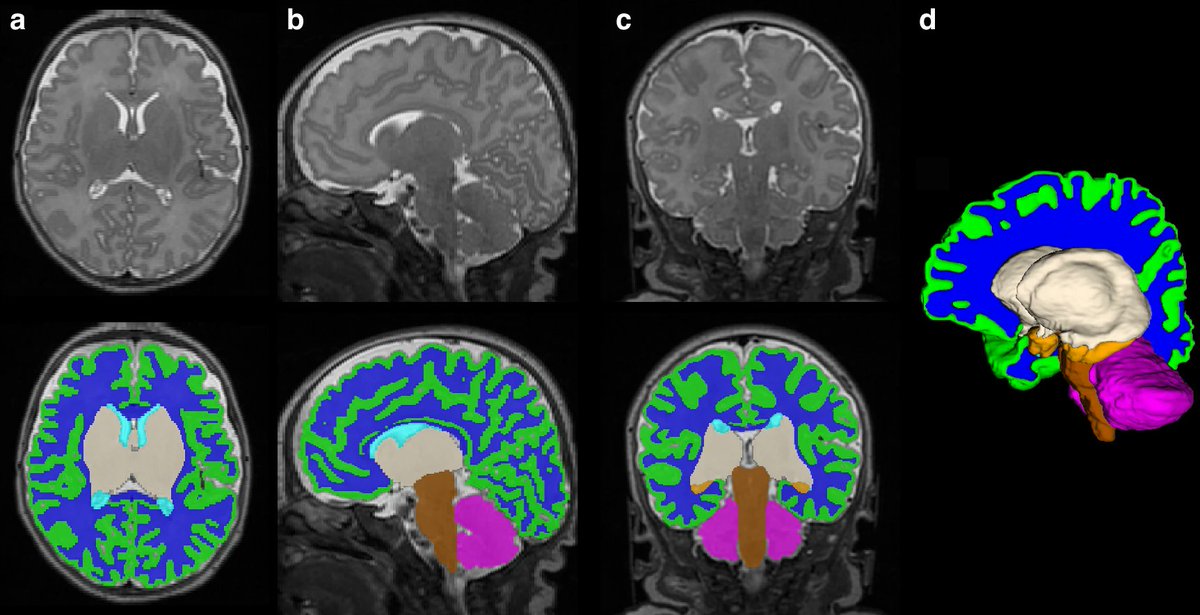

Donor Human Milk & brain development n=152 <32w (67 MOM, 44 DHM, 41 PTF) DHA & MOM ↔️ brain volume & WM microstructure PTF ⬇️ volume & more microstructure alterations MOM ⬆️ ex-utero 3rd trimester brain dev DHM -> potential advantage brain develop https://t.co/qGGqeE2W2W